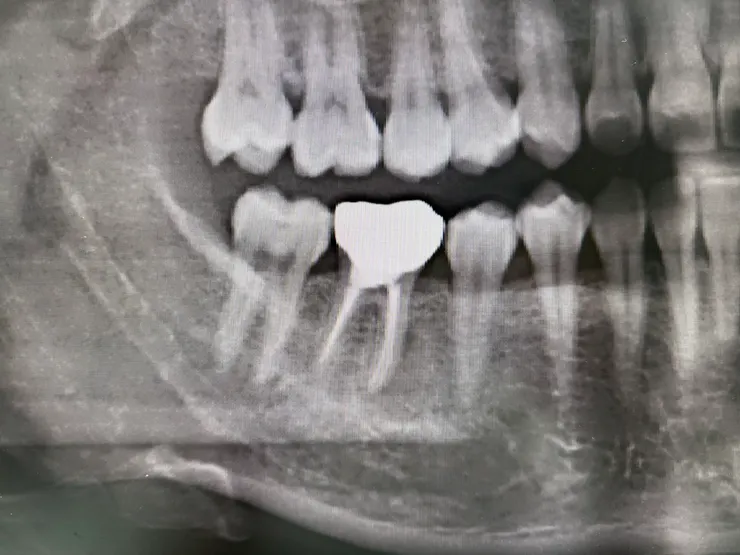

環口X光

單張X光